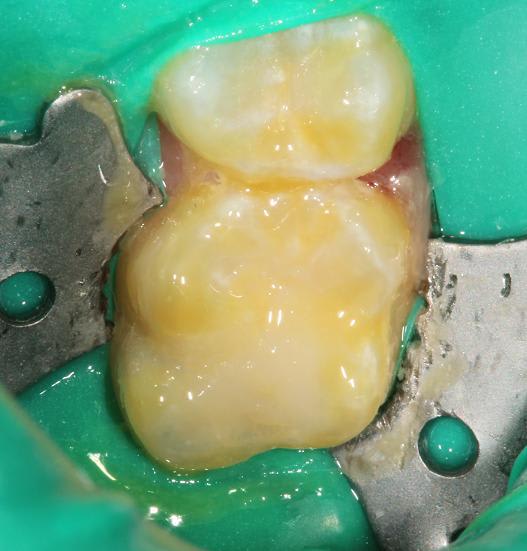

J'utilise le protocole suivant dans le cas d'effraction pulpaire sur dents permanentes immatures (en général des 1ères molaires à 6-10 ans). J'aimerai le soumettre à vos critiques.

1 : cavité et effraction.

2 : coiffage au MTA.

3 : nettoyage du pourtour avec une fraise boule sans spray sur CA.

4 : fond de CVI pour pouvoir mordancer sans dissoudre le MTA.

5 : restauration composite.

6 : fluoration Duraphat.

Toto, j'utilise la technique simplifiée de la "digue fendue" ("split dam" en anglais) qui est bien adaptée à la denture temporaire et mixte. Ici, la perforation est bloquée entre 24 et 25 de façon étanche : tu peux remarquer que même en prenant le temps de photographier chaque étape, il n'y a pas une seule goutte de salive dans le champ.